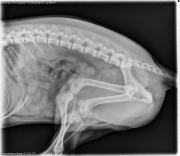

Today’s case is a 7 month old Miniature Schnauzer with history of straining to urinate after trauma to the ventral abdomen. Post your comments below!

R LAT Abdomen

There are no abnormalities involving the abdomen or urinary tract on the precontrast lateral radiograph.

A contrast urethrogram was performed. A Foley catheter was placed in the distal urethra and the balloon inflated. Non-ionic contrast medium was injected, and several radiographs were taken during this procedure. There is a focal narrowing of the urethra 1 cm caudal to the os penis. This narrowed area is visible on both contrast projections.

• Urethral stricture

Urethral strictures may form secondary to trauma or lodged calcluli. The normal urethra narrows through the pelvis, then widens slightly at the prostate gland. True narrowing or filling defects should be visible on multiple images. Air bubbles can mimic filling defects but will move to different locations in the urethra as contrast is injected. It’s important to take several radiographs as contrast is injected to differentiate between true lesions and artifacts.